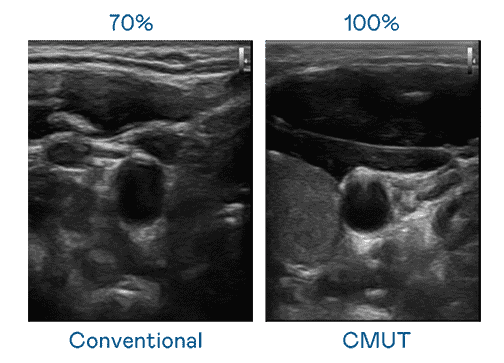

CMUT 技术是一种用电容式微机电元件来产生超音波讯号的技术。。。。与传统 PZT 压电式技术相比,,,,CMUT 频宽增加 30%,,,更宽频的超音波讯号让影像解析度大幅提升,,是实现高影像品质医疗超音波扫描、、、促进精准医疗发展的关键技术。。。。

大频宽带来超清晰影像

超音波影像的解析度高低,,首先取决于探头能发出的讯号频宽。。。。口袋牛店 CMUT 可提供高清晰的超音波讯号,,,,提供高频宽、、、高灵敏度、、、影像纹理细节更高的超音波影像,,协助医护人员缩短影像判读时间及利用精准的医疗影像进行诊断。。